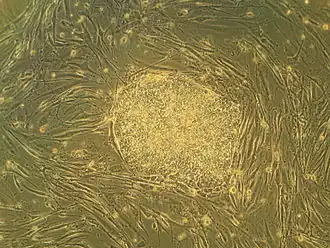

The discovery of insulin at the University of Toronto by Banting and Best in 1921 is considered among the most significant events in the history of medicine.[14][160] The stem cell was discovered at the university in 1963, forming the basis for bone marrow transplantation and all subsequent research on adult and embryonic stem cells.[161] This was the first of many findings at Toronto relating to stem cells, including the identification of pancreatic and retinal stem cells.[162][163] The cancer stem cell was first identified in 1997 by Toronto researchers,[164] who have since found stem cell associations in leukemia, brain tumours and colorectal cancer.[165][166] Medical inventions developed at Toronto include the glycaemic index,[167] the infant cereal Pablum,[168] the use of protective hypothermia in open heart surgery[16] and the first artificial cardiac pacemaker.[16] The first successful single-lung transplant was performed at Toronto in 1981, followed by the first nerve transplant in 1988,[169] and the first double-lung transplant in 1989. Researchers identified the maturation promoting factor that regulates cell division, and discovered the T-cell receptor, which triggers responses of the immune system.[170] The university is credited with isolating the genes that cause Fanconi anemia, cystic fibrosis and early-onset Alzheimer's disease, among numerous other diseases.[171] Between 1914 and 1972, the university operated the Connaught Medical Research Laboratories, now part of the pharmaceutical corporation Sanofi-Aventis. Among the research conducted at the laboratory was the development of gel electrophoresis.[172]